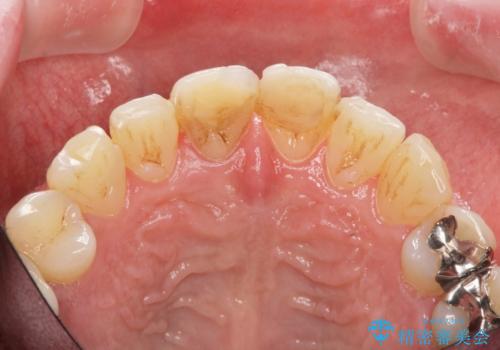

前歯の変色を改善!セラミック治療

- 前歯の変色が気になり審美障害の改善を求めて来院されました。

根管治療に伴う歯の色調変化はよく見られる所見です。

セラミッククラウン製作を行い審美性の改善を計画します。

周囲の歯の色調に合わせた、自然なセラミック治療を行うことができましt。